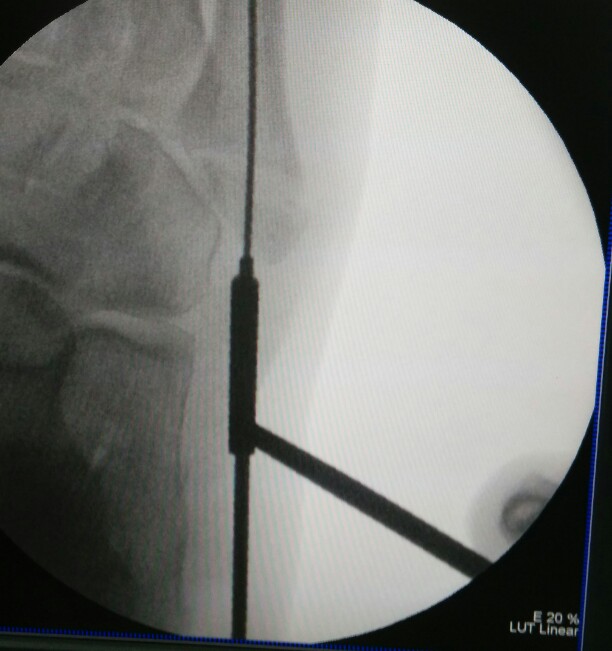

Percutaneous cannulated screw fixation of this displaced avulsion fracture of the 5th metatarsal base was performed.

This procedure is done via a small incision and guided by x-rays fluroscopy.